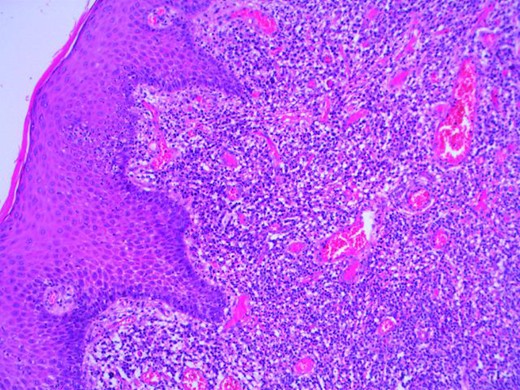

At operation, examination of the perianal area identified three right-sided anal fissures, the largest of which was at ‘10 o’clock’ in the lithotomy position. The fissures had a chronic appearance with a broad, pink base and somewhat ‘velvety’ texture. The surrounding squamous epithelium was dotted with focal areas of whitish macular discolouration. Proctoscopy and rigid sigmoidoscopy did not reveal any other pathology. The fissures were debrided of chronic inflammatory tissue to encourage active wound healing and, given their atypical appearance, biopsies were taken for histology. Histological examination diagnosed spirochaete infection (see Figs 1–2). The patient was followed up in clinic, treated with penicillin and advised regarding contact tracing of previous sexual partners.

Microscopy photograph from the histological specimen; perianal skin tissue with localized plasma cell rich inflammation.